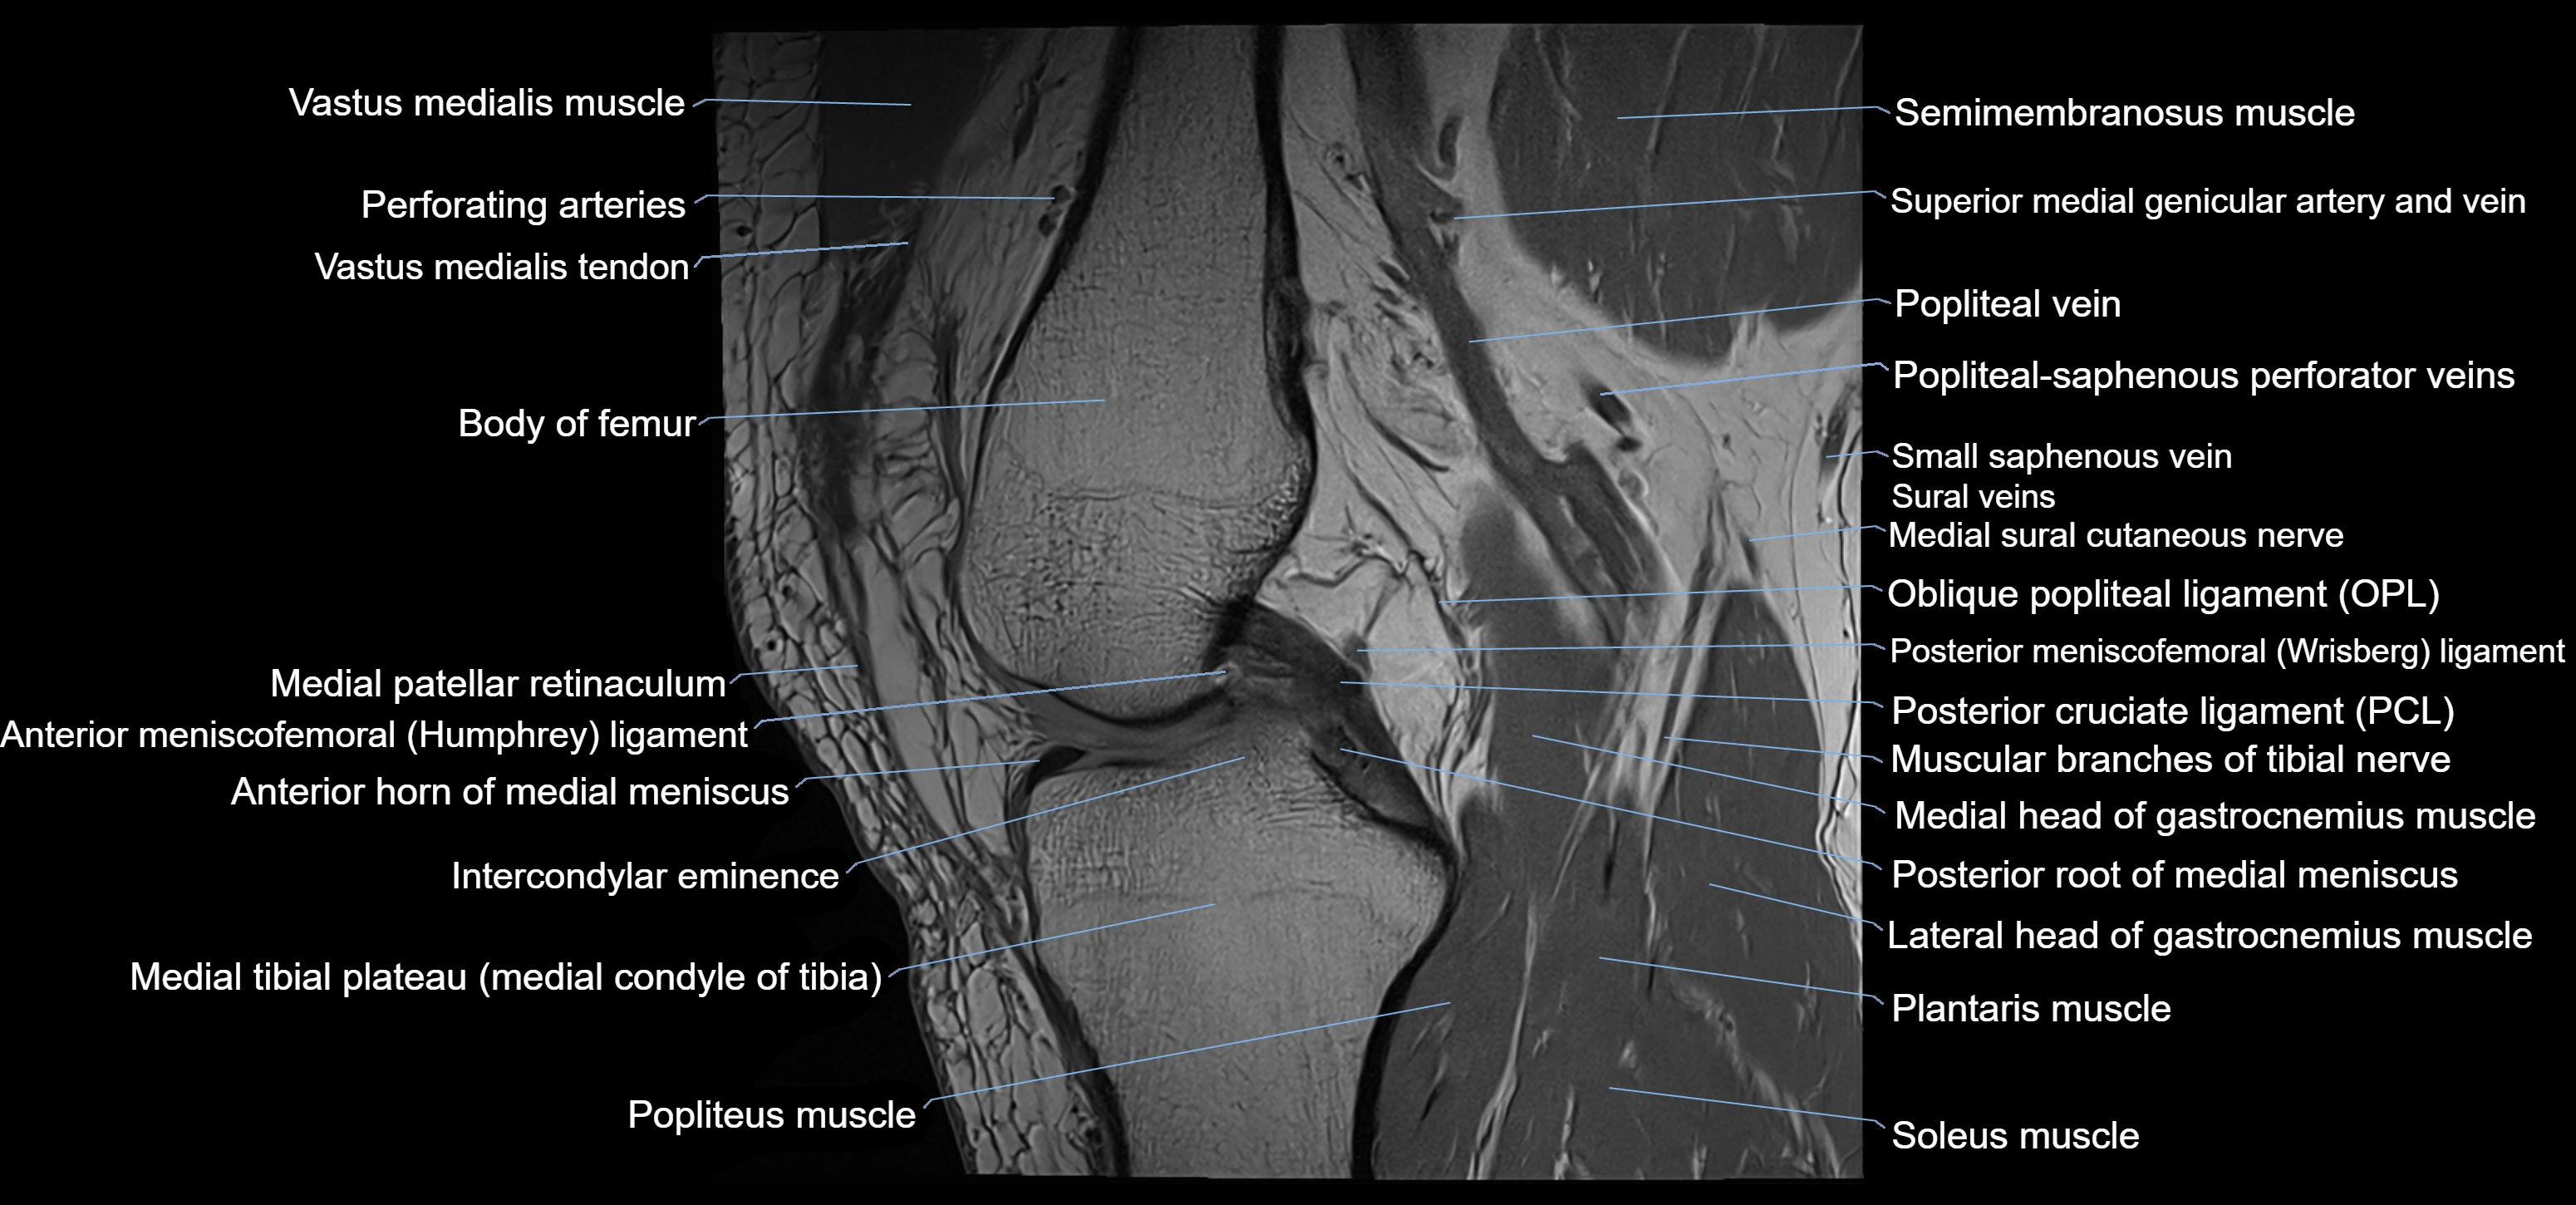

- Anterior horn of medial meniscus

- Anterior meniscofemoral ligament

- Intercondylar eminence

- Medial collateral ligament

- Medial head of gastrocnemius muscle

- Medial meniscus

- Medial patellar retinaculum

- Medial tibial plateau

- Muscular branches of tibial nerve

- Oblique popliteal ligament

- Popliteus muscle

- Posterior cruciate ligament

- Posterior horn of medial meniscus

- Posterior meniscofemoral ligament

- Posterior root of medial meniscus

- Semimembranosus muscle

- Soleus muscle